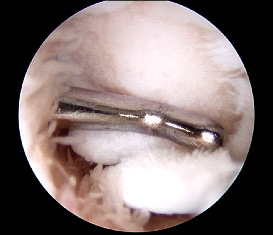

Step 2: damaged cartilage cleared

leaving bare bone